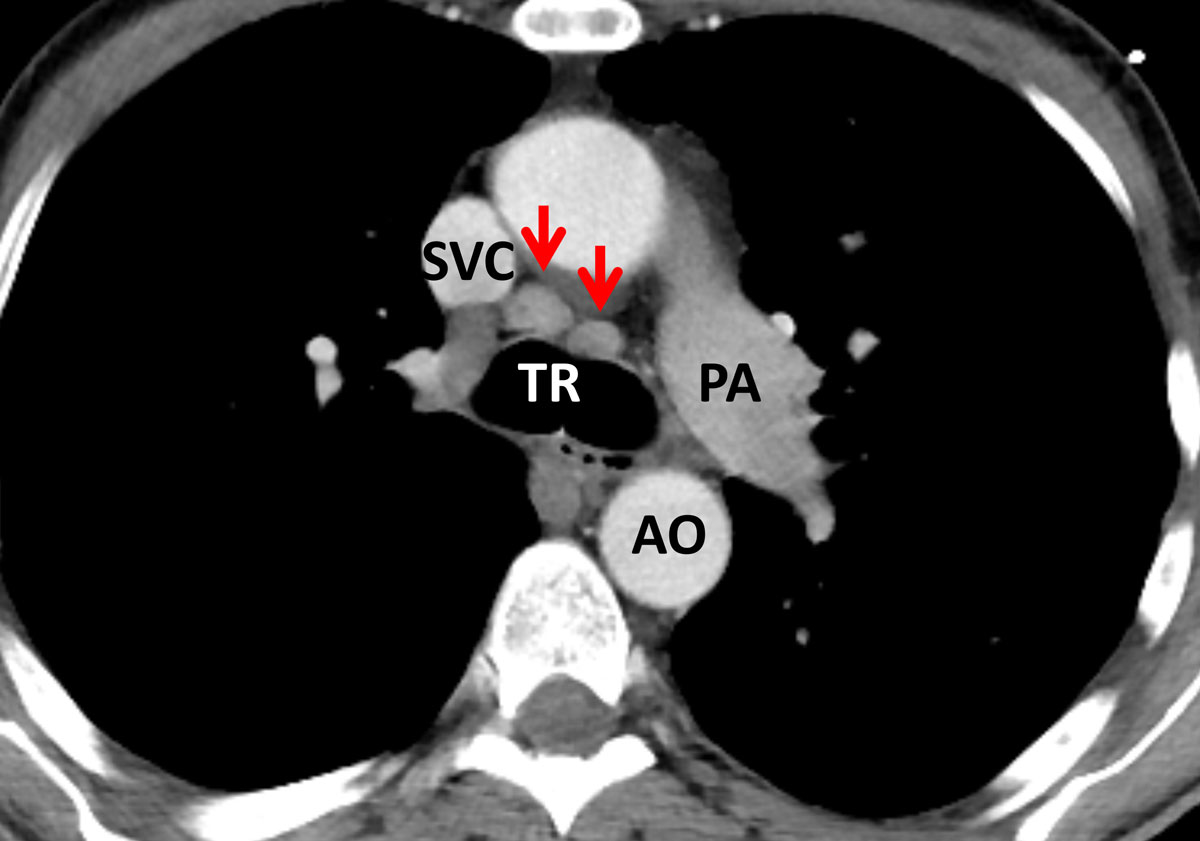

In comparison, the HIV-positive patients with PJP showed significantly more areas of atelectasis (41.7 ± 6.4%, vs 4.2 ± 4.1% in RTRs, p = 0.017; table 2). Furthermore, HIV patients tended to present with a more “classic” pattern of PJP, exhibiting subpleural sparing (fig. 2) and additional hilar lymph node enlargement (23.3 ± 5.5%; fig. 3). Pneumothorax formation was restricted to 3.3% of the HIV-positive patients. When the results from the conservative Bonferroni method were compared with the results from a multi-variable analysis, significantly more cysts could be found in HIV than in RTR cases (15.0 ± 4.6% vs 4.2 ± 4.1%, p = 0.038; table 2). An analysis of the disease distribution within each lung segment between the two cohorts did not yield any statistically significant results (table 2).

Figure 3 Axial cross section image in soft tissue window at the level of the carina in a human immunodeficiency virus (HIV)-positive patient with Pneumocystis jirovecii pneumonia (PJP). There is mediastinal lymph node enlargement at the left and right lower paratracheal nodal stations (arrows). Although not specific for PJP in HIV-positive individuals, mediastinal lymph node enlargement was more frequent in this patient population. TR = trachea; SVC = superior vena cava; PA = pulmonary artery; AO = aorta